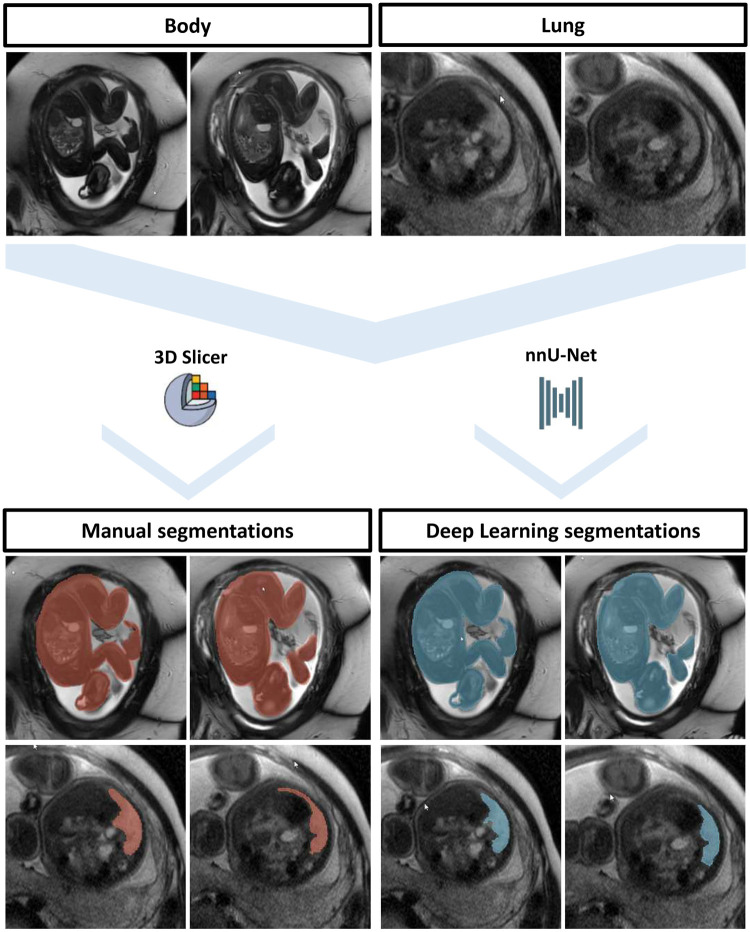

Purpose: To determine if deep learning (DL) segmentation of total fetal body volume (TFBV) and total fetal lung volume (TFLV) in fetuses with congenital diaphragmatic hernia has comparable performance to manual segmentation.

Materials and methods: A total of 208 fetal MRI studies with congenital diaphragmatic hernia, acquired between August 2007 and September 2023, were retrospectively included. TFBV and TFLV were extracted from manual tissue segmentations in balanced gradient echo and single shot T2-weighted turbo spin echo sequences. MRI studies were split into training (n = 188) and hold-out test data (n = 20). Wilcoxon signed-rank test was used to compare manual and DL-based segmentations by 2 U-Nets. Manual and DL segmentation times were noted and compared using Student's t-test. The observed/expected ratio of the total lung volume (O/E TLV) as a prognostic marker for postnatal survival was calculated. Outcome predictions of O/E TLV for postnatal death were assessed with univariate regression analysis.

Results: Manual segmentation times were higher compared to DL segmentations (30 ± 7 minutes versus 0.25 ± 0.05 minutes, P <.001). Manual and DL-based TFBV were similar (1317 ± 498 mL versus 1306 ± 491 mL; P = .04; Dice score: 0.98 ± 0.01). TFLV (19.4 ± 11.5 mL versus 18.7 ± 12.4 mL; P = .11; Dice score: 0.84 ± 0.09) and O/E TLV (39.3 ± 18.1 mL versus 37.7 ± 19.1 mL, P = .13) were not significantly different. Postnatal mortality was negatively associated with higher manual O/E TLV (odds ratio: 0.97; 95% confidence interval [CI], 0.96-0.98; P <.001) and DL O/E TLV (odds ratio: 0.97; 95% CI, 0.96-0.98; P <.001).

Conclusion: DL for body and lung segmentation in fetuses with congenital diaphragmatic hernia allows reliable and rapid calculations of the observed/expected ratio and equally predicts prognostic outcome.